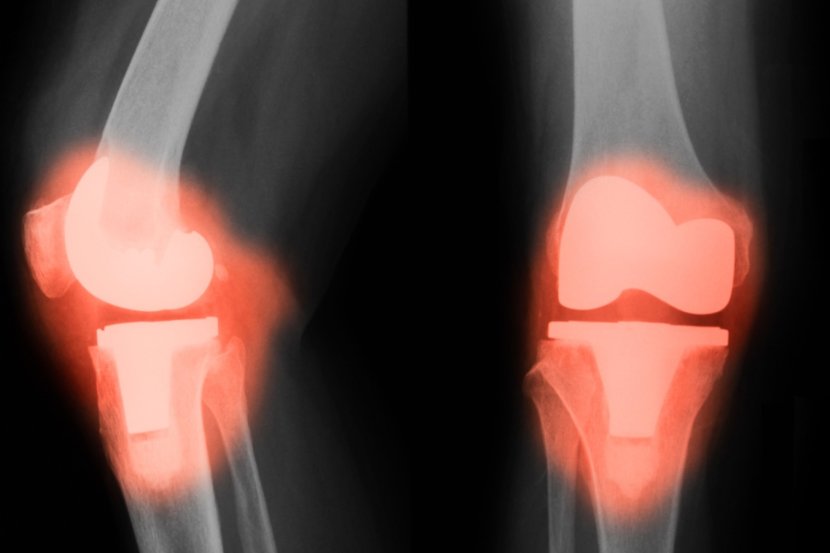

Nova studija otkriva da će pacijenti koji se podvrgavaju uobičajenoj operaciji zamene velikih zglobova doživeti povišene nivoe nekih metala u krvotoku i moždanim i kičmenim tečnostima zahvaljujući prisustvu zglobnih implantata, što izaziva zabrinutost zbog rizika od dugoročnih štetnih neuroloških efekata.

Pilot studija NeuroWear, nedavno objavljena u JAMA Network Open, procenila je 103 osobe sa zglobnim implantatima u poređenju sa 108 onih bez njih. Otkrili su da pacijenti sa implantatima imaju veće koncentracije metala u krvi i cerebrospinalnoj tečnosti (CSF), što ukazuje na to da metali iz implantata – posebno kobalt – mogu da pređu u centralni nervni sistem.

Titanijum i kobalt-hrom trenutno su najčešći metali koji se koriste u proizvodnji protetskih zglobova. Legure kobalt-hrom-molibden poznate su po svojoj čvrstini, izdržljivosti i otpornosti na koroziju, što ih čini popularnim izborom za metalne komponente u zamenama zglobova, posebno u protezama kuka i kolena. Međutim, ovi zglobovi mogu sadržati i keramičke materijale, kao što su alumina i cirkonijum, za određene komponente, posebno kod zamena kuka, radi poboljšane otpornosti na habanje i biokompatibilnosti.